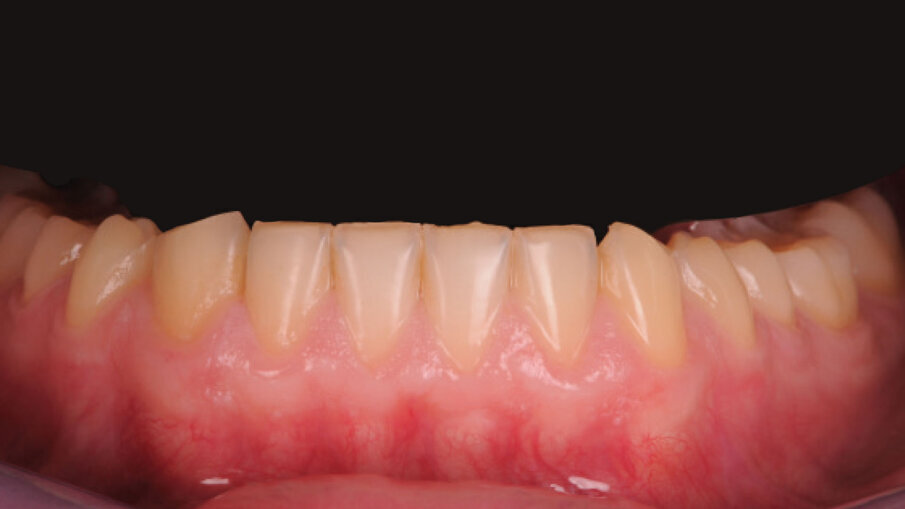

Paziente maschio di anni 26, si presenta alla prima visita con una esplicita richiesta di miglioramento estetico, in quanto non soddisfatto dei suoi denti e di conseguenza del suo sorriso. All’anamnesi riferisce di sorridere poco e con difficoltà, limitando la sua socialità1. Risulta fondamentale in questi casi la fase del colloquio iniziale, per far emergere gli aspetti che il paziente ritiene sgradevoli e cosa invece lo farebbe sentire a suo agio. Si utilizza la fase iconografica dimostrativa con fotografie eseguite su casi simili già finalizzati per mostrare al paziente le fasi cliniche e le possibili soluzioni alle sue richieste. Bisognerà dedicare molto tempo ad ascoltare il paziente, i suoi dubbi e le sue esigenze, capendo da subito le sue aspettative prima di impostare il piano di trattamento. L’esame clinico intraorale, mostra un’arcata superiore con microdonzia a carico degli incisivi laterali 12 e 22, con diastemi e volume ridotto degli elementi canini in proporzione alla dimensione ossea strutturale. Il termine microdonzia2 è spesso abusato, poiché non vi sono dei parametri che la letteratura indica per definire tale situazione, spesso gli elementi microdontici lo sono in rapporto agli altri elementi dentali come in questo caso. Gli elementi 11 e 21, originariamente normo formati, presentano irregolari abrasioni della superficie vestibolare probabilmente causate da tecniche di spazzolamento incongrue che hanno esposto delle isole di dentina vestibolare3 (Figg. 1-3).

Alterazioni dell’anatomia inoltre si evidenziano anche a livello dei margini incisali dove sono evidenti delle micro fratture a carico dello smalto, originate da un probabile sovraccarico occlusale. Andando alla ricerca di una possibile causa di questo tipo di alterazione morfologica, un’attenta analisi dei gruppi posteriori evidenzia anche qui una situazione inusuale, cioè un’evidente riduzione dello smalto della porzione occlusale degli elementi diatorici specificamente dei premolari e dei primi molari, con conseguente alterazione dell’anatomia, mentre un normale sviluppo e una normale conformazione occlusale degli ultimi molari 37 e 47. Completando la visita e concludendo l’analisi con il V sestante si nota una inevitabile abrasione a carico dello smalto degli incisivi inferiori con usura dei canini soprattutto sul lato destro dove il canino in posizione 43 risulta riportare un’abrasione molto importante a differenza del 33 che appare normo conformato (Fig. 4). Emerge quindi che la situazione intra orale mostra alcuni elementi con alterazioni congenite come gli incisivi laterali e altri elementi con alterazioni acquisite di natura erosiva-abrasiva. In entrambi i casi il percorso da seguire è quello di, studiare le forme dentali residue per “reintegrarle” basandosi sugli elementi integri, utilizzati come guida per una riabilitazione “anatomicamente” guidata.